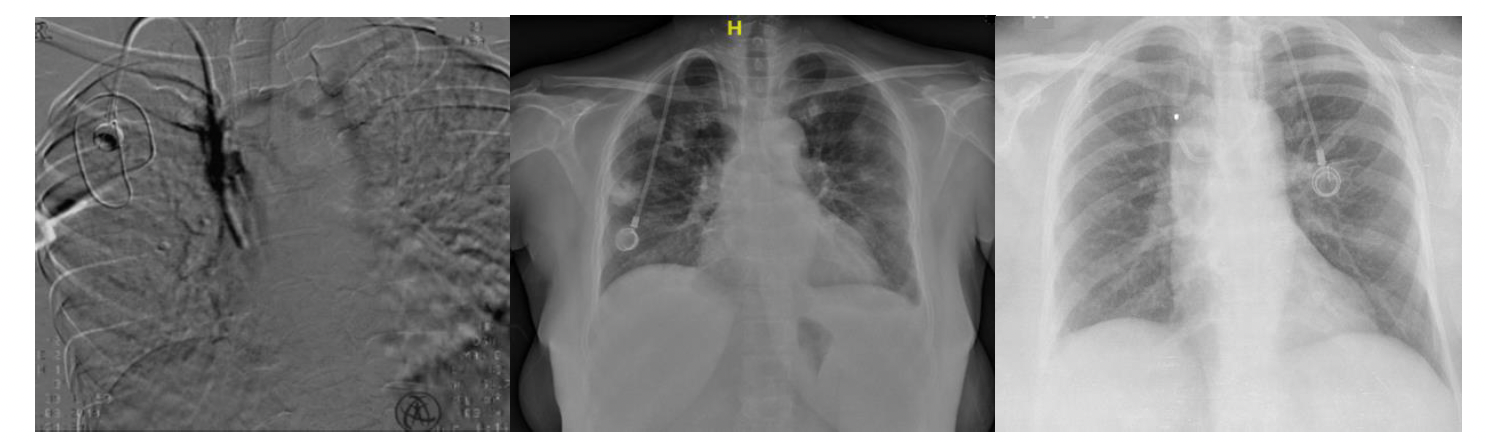

A chemoport, or central venous port (CVP), is a venous access device that is entirely implanted under the skin, most commonly on the anterior chest wall1 (Figure 1). The first report of subcutaneous tunneled CVP placement in 19822 was described by a surgeon, and the first successful radiologically inserted chemoport was reported by Morris et al3 in 1992. Since then, chemoports have been widely used in treating oncology patients requiring repeated intravenous administration of chemotherapy as they provide long-term venous access that is safe, easy, durable, and cosmetically accepted by oncology patients.4,5

Postprocedure fluoroscopy image or chest radiograph was routinely taken to reconfirm the position and to look for any kinks or migration (Figure 2). The sutures were removed after 10 days in the ward or the IR suite. The chemoports were flushed with heparinized saline after each cycle of chemotherapy.

Fifteen patients (1.48%, 0.041/1000 catheter days) developed catheter dysfunctions (11 thrombotic and 4 nonthrombotic). Only 1 out of 11 thrombotic dysfunctions developed early, which occurred after 27 catheter days. The patient developed catheter occlusion, which was proven on a patency check done in the IR suite. Five out of 11 ports were explanted (port removal for fibrin sheath formation shown in Figure 4) and the remaining 6 were successfully treated with thrombolysis with urokinase (Figure 5). The thrombotic complication with fibrin sheath formation occurred as late as 1206 days, which was treated with thrombolysis using urokinase.

There were 3 catheter migrations and 1 port rotation. Catheter migrations (Figure 4) were noticed to migrate into the right IJV, right brachiocephalic vein, and left subclavian vein. All these patients underwent explantation and reinsertion of the ports. One of the patients whose port was migrated to the right IJV was admitted for chemoport removal and reinsertion. However, during the manipulation of the displaced port catheter, she began experiencing severe rigors in the IR suite. She was afebrile and hemodynamically stable; the procedure was abandoned, the port removed, and the patient shifted to the ward immediately. Cultures were drawn and she was started on I.V. cefoperazone-sulbactam, along with teicoplanin. She went into septic shock that evening and I.V. cefoperazone-sulbactam was changed to injected. Meropenem at a 2-g loading dose was followed by 1 g every 8 hours. She was resuscitated with fluids and remained hemodynamically stable afterward. One port rotation in the chest wall was incidentally detected on a follow-up computed tomography (CT) scan of the chest, but the patient had already completed chemotherapy so no treatment was sought.